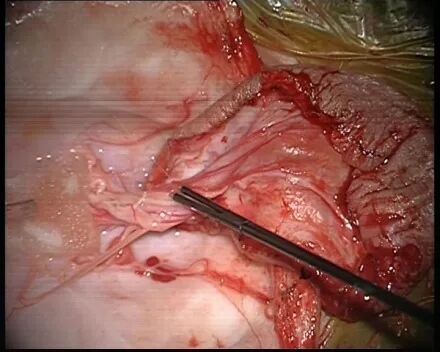

4. 鉴别并分离神经板、神经根,10-0 prolene线缝合神经板。技术要点:术中电生理监测,锐性分离,少用电凝。

5. 扩大修补硬脊膜。技术要点:扩大并无张力下修补,以6-0prolene线硬脊膜包边Asculap Neuro-Patch补片间断包边严密缝合。